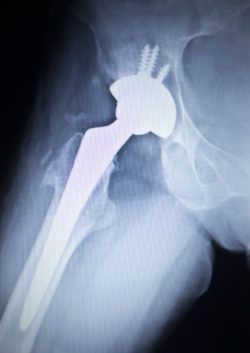

Stryker metal hip implant recallA Massachusetts man is filing a Stryker recall lawsuit claiming that he experienced significant injuries as a result of his allegedly defective Stryker hip implant system.

On two different occasions, plaintiff Joseph D. says he was implanted with the Stryker Accolade hip replacement system and a V40 femoral head. He was implanted in his left hip on Dec. 4, 2008 and in his right hip on Feb. 19, 2009.

The surgeon also found the presence of corrosion at the taper junction between the Accolade stem and Stryker’s L-FIT V40 Chromium Cobalt femoral head.